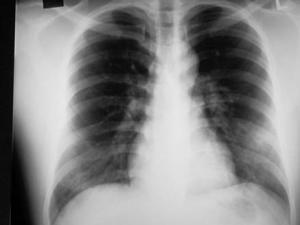

肺水肿(pulmonary edema)是一种肺血管外液体增多的病理状态,浆液从肺循环中漏出或渗出,当超过淋巴引流能力时,多余的液体即进入肺间质或肺泡腔内,形成肺水肿。本病可并发于多种疾病,病情常危重,应积极抢救。[1]